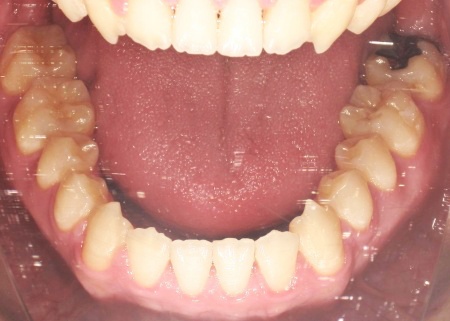

20代男性 受け口のように見える切端咬合をセラミックブラケットによる矯正治療で改善した症例

拝見したところ、上下前歯の先端同士が触れ合う「切端咬合(せったんこうごう)」の状態でした。

通常は上前歯が下前歯をわずかに覆うように重なりますが、患者様の場合は上下前歯の先端がほぼ同じ高さで噛み合っているため、受け口のような印象がみられました。